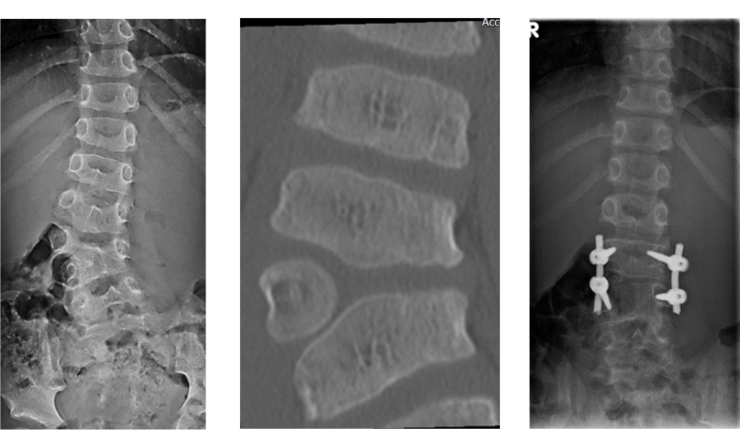

Beispiel eines lumbalen Halbwirbels bei einem 5 jährigem Jungen:

Bei angeborenen Knochenfehlbildungen helfen weder Krankengymnastik noch eine Korsettbehandlung. Auch die Operation verläuft ganz anders. In der Regel wird schon im frühen Kindesalter zwischen dem 2. und 5. Lebensjahr die Fehlbildung behoben, da sich ansonsten die angrenzenden Wirbelkörper verformen. Dabei wird zum Beispiel ein Halbwirbel entfernt. Es muss aber nicht langstreckig versteift werden, sondern nur der fehlgebildete Bereich behandelt werden.